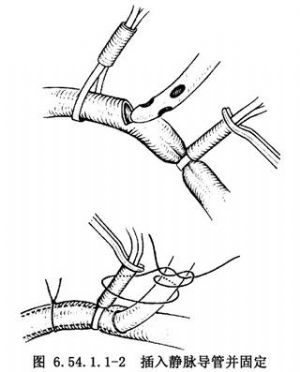

大腿稍外旋,自腹股沟韧带稍上方开始,沿股动、静脉走向,向远侧做10cm长纵行切口,解剖出股动、静脉并分别在其近、远侧绕阻断带暂时阻断血流。将股静脉横行剪开达周径之半(图6.54.1.1-1),插入有侧孔的F32~36号静脉导管,向近侧一直插入至下腔静脉,收紧阻断带,固定导管(图6.54.1.1-2)。并以适宜口径的导管做股动脉插管,导管尖端置于髂总动脉内。肝素化后开始部分转流(图6.54.1.1-3)。在流量仅达1000ml/min时病人情况即会明显改善,此时即可行全身麻醉气管插管。